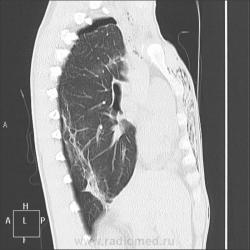

Правосторонний гемопневмоторакс .Подкожная эмфизема передней грудной стенки справа.

Раневой канал отвёртки интересный, раньше не встречалось, вот и выставила. Длина канала 12 см. Всё верно, малый гемопневмоторакс, пневмомедиастинум, межмышечная эмфизема.

Раневой канал в виде четкого округлого дефекта в правом легком, начинается от 4-го межреберья по паравертебральной линии справа, идёт кпереди и немного кверху, заканчивается слепо на уровне середины просвета трахеи (справа от неё).

Учитывая, что весь сагитальный размер грудной клетки на уровне раны 18 см (щуплый юноша), можно сказать, что пациент легко отделался...

Пневмомедиастинум. Воздух собирается, где ему вздумается, и пациент так и лежал на животе с поступления - на спине рана, обработка....

Трахея повреждена значит вероятен пневмомедиастинум.Ну совсем небольшой.

Нет, Евгений. Трахея не повреждена, вохдух из плевральной полости в средостение поступает при травмах очень часто. Необязательно повреждение верхних дыхательных путей.

Смотрите внимательней.. раневой канал не заканчивается слепо. Он заканчивается точно в просвете трахеи.И воздух в средостении будет увеличиваться.распространится на шею.

Евгений, перед лицом своих товарищей торжественно клянусь: раневой канал заканчивается слепо в 1 см от правой боковой стенки трахеи

Объем 200 мл, плотность 60-68 ед.Н.